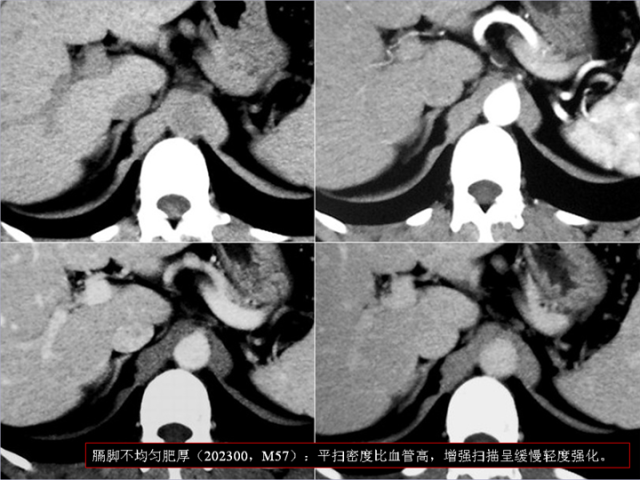

膈肌角解剖及常见变异

作者:王俭 上海长征医院